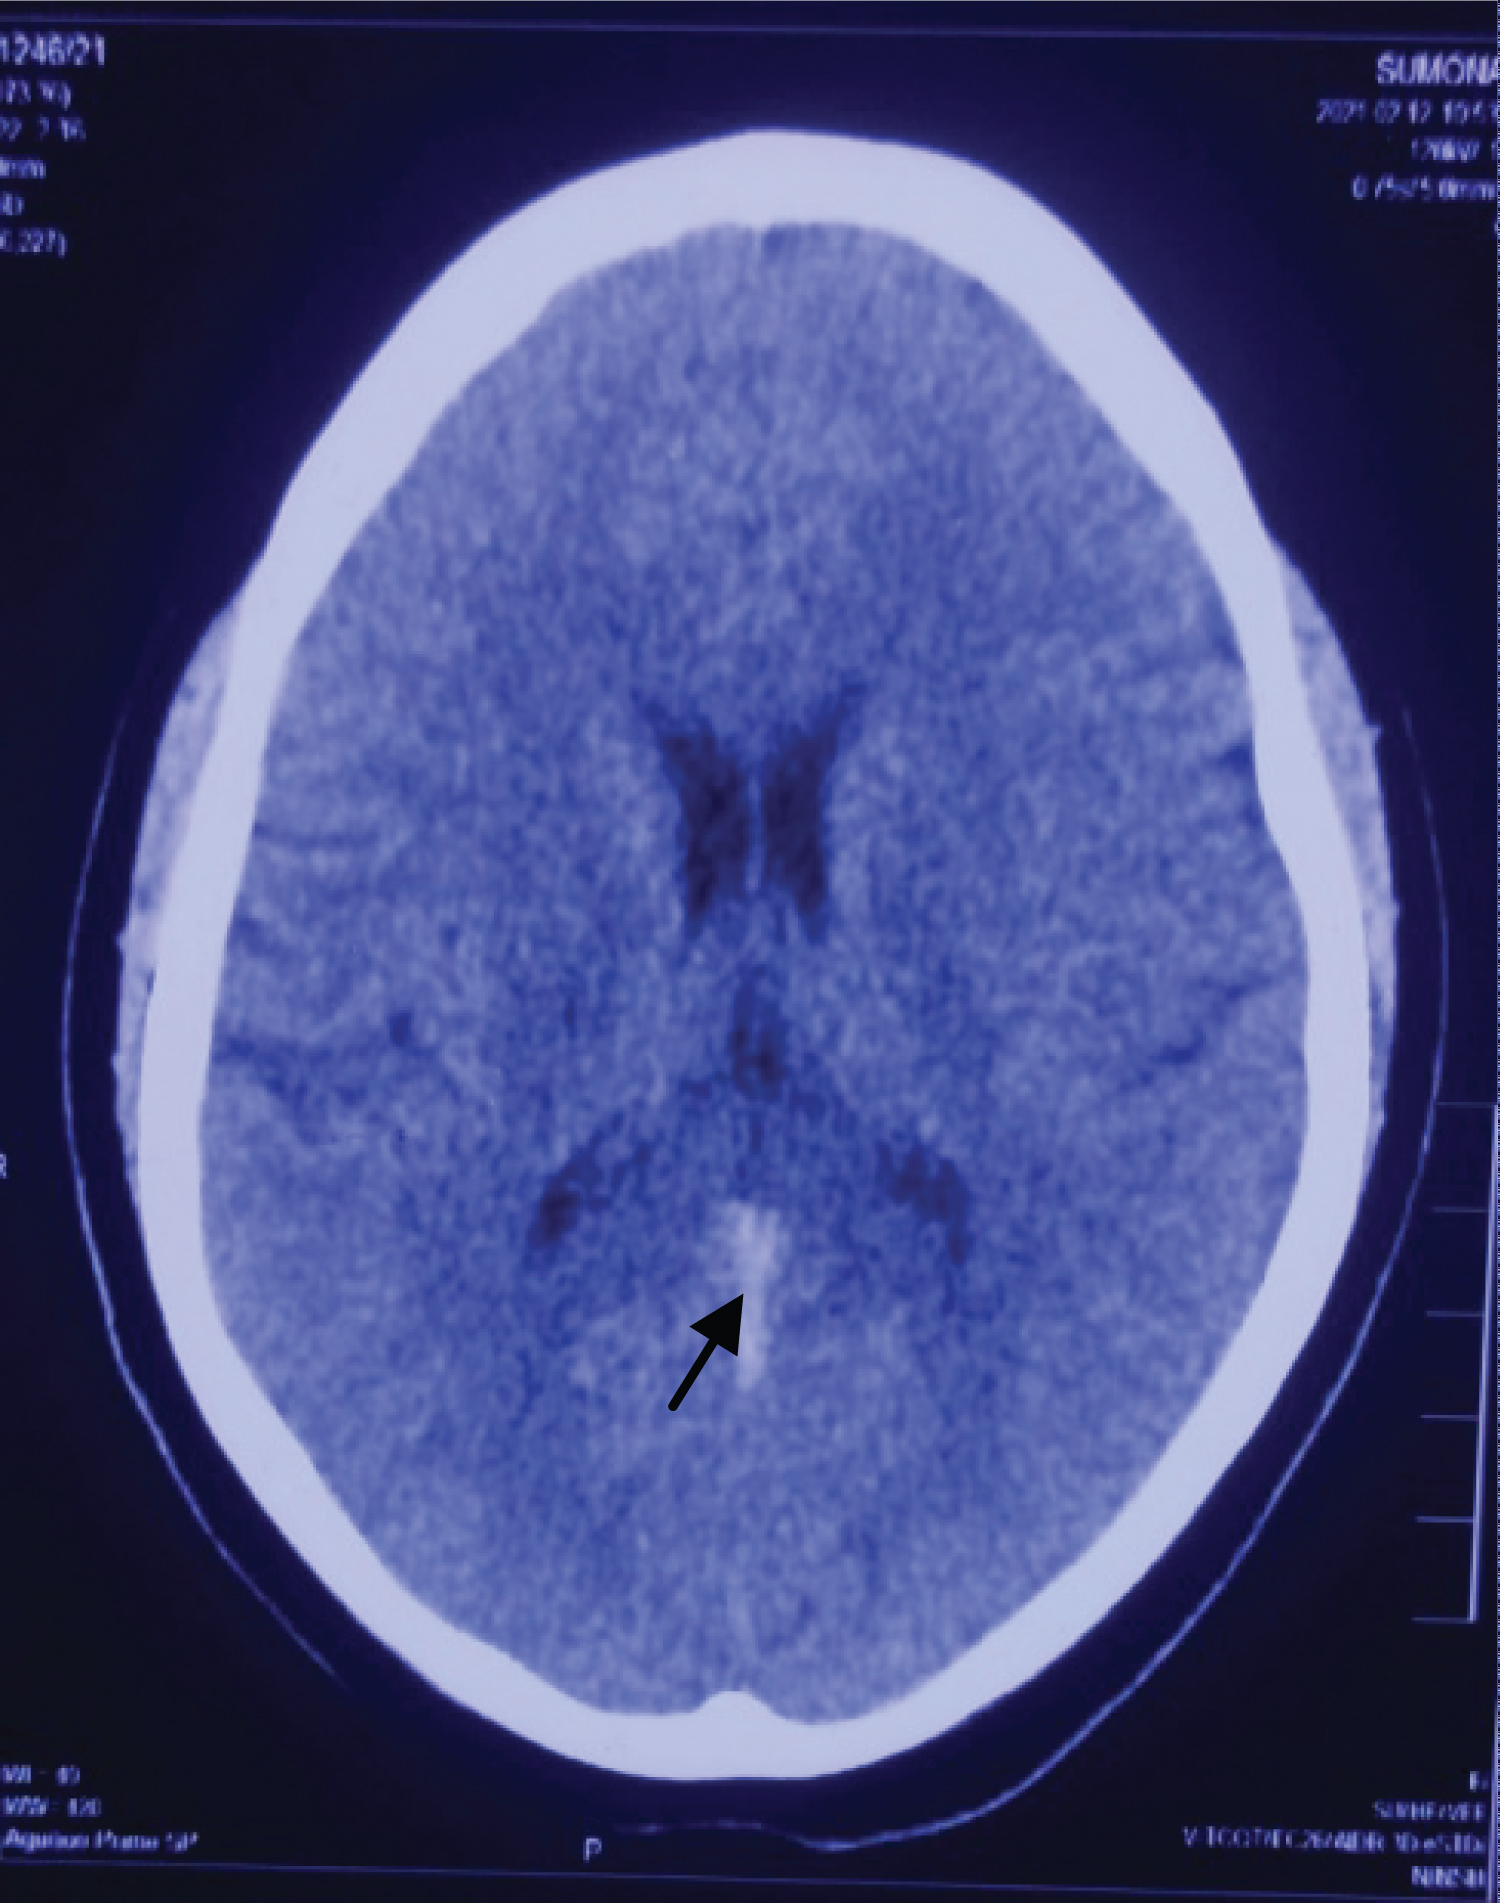

Initial laboratory investigations revealed normal blood counts, as well as kidney and liver function. Electrocardiography revealed sinus tachycardia. Thyroid function tests revealed a serum Thyroid-Stimulating Hormone (TSH) level < 0.004 μIU/mL (normal 0.350-5.50 μIU/mL), free thyroxine (FT4) 4.2 ng/dL (normal 0.7-1.8 ng/dL), and free tri-iodothyronine (FT3)- 6.45 ng/dL (1.4-4.2 ng/dL). Anti-thyroid peroxidase (anti-TPO) was > 2000 IU/mL (normal 5-20 IU/mL). TSH-receptor Ab was 59.4% (normal < 16%) Thyroglobulin antibody (Ab) was within normal limit. Tests for other autoimmunity markers (antinuclear, ENA profile, ANCA) were negative. Laboratory tests performed for the assessment of a hypercoagulable state revealed the following results:, d-dimer 5.74 μg/mL(normal < 0.55 μg/mL), fibrinogen 554.5 mg/dL (normal 200-400 mg/dL). No changes were found in any other proteins tested (antithrombin III, protein C, protein S, Factor V Leiden, von Willebrand factor, lupus anti coagulant, anti cardiolipin antibody, homocysteine). Factor VIII level was not done due to unavailability. Brain Computed Tomography (CT) revealed dense triangle/vein sign (Figure 1). Brain Magnetic Resonance Imaging (MRI) with Magnetic Resonance Venography (MRV) was performed which revealed CVST involving right transverse, right sigmoid sinus and straight sinus resulting in small acute infarct in mid part of splenium of corpus callosum (Figure 2). Ultrasonography of thyroid revealed diffuse enlargement of both thyroid lobe with increased vascularity. Thyroid scan revealed diffuse homogenous uptake of radioactive tracer in both thyroid lobes suggestive of Graves disease (Figure 3).

Figure 1: CT brain showing dense vein/triangle sign (arrow head). View Figure 1

Diagnostic radiological findings in patients with CVST include the following: venous sinus thrombosis can be identified as a hyperdensity lesion of the affected sinus for the first 7-14 days on non-enhanced CT images. Following contrast administration, CVST presents as a filling defect in a sinus, and patients with involvement of the sagittal sinus and transverse sinus typically show the 'empty delta sign' and dense vein/triangle sign with or without cord sign respectively. Reportedly, CT venography shows a sensitivity of 95% in these cases. MRI can help in visualization of the clot as well as the sequelae. The clot shows variable signal intensity based on its stage (acute-to-chronic stage). During the acute stage, the clot appears isointense on T1WI and hypointense on T2WI, and during the subacute stage the clot appears as a hyperintense lesion on T1WI. Notably, clots can be easily detected as a dark signal within areas of hemorrhage (typically described as blooming artifacts) on T2* GRE or susceptibility images. Venous infarction can be identified on DWI. Contrast-enhanced MR or MR venography shows greater sensitivity in detecting thrombosis, which presents as a venous filling defect in patients with CVT.

Although initial laboratory investigations revealed poorly controlled thyroid hormone levels indicating thyrotoxicosis, the diagnosis of CVST was delayed in this patient until confirmatory MR venography was performed. Any further delay in diagnosis could have led to irreversible neurological injury even with optimal treatment. This case emphasizes the importance of careful evaluation for early diagnosis of venous thrombosis in young adults with hyperthyroidism presenting with unexplained neurological symptoms. Clinicians should be aware that further evaluation to confirm CVST should be considered with CT or MR angiography with venous phase and blood-sensitive MR sequences, such as T2* GRE or susceptibility weighted imaging in patients with a suspicious hyperdensity or the empty delta sign/cord sign/dense vein sign in the cerebral venous sinuses on brain CT.